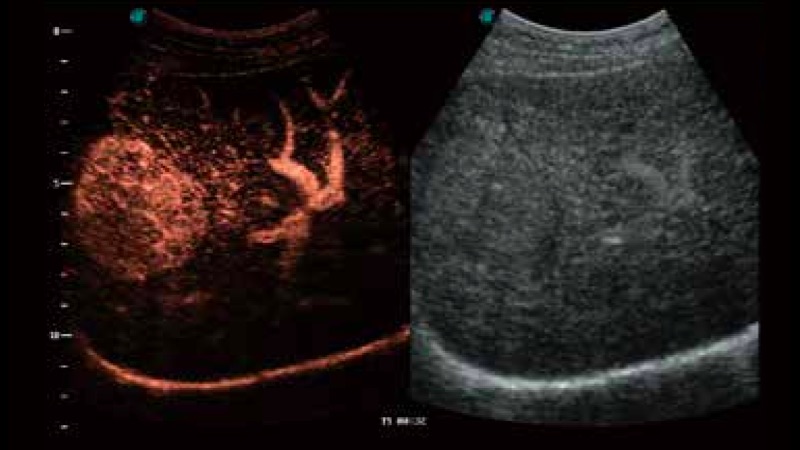

開立醫(yī)療通過不斷的技術(shù)創(chuàng)新,為大眾的生命健康提供持續(xù)關(guān)愛。P12 Plus采用全新一代超聲成像平臺,新平臺旨在將真實(shí)還原組織解剖結(jié)構(gòu)作為首要目標(biāo)。平臺采用全新集成化硬件模塊,搭載新一代芯片,系統(tǒng)性能得到大幅提升,為您的診斷提供了豐富的臨床信息。優(yōu)異的圖像表現(xiàn),豐富的探頭配置,全面的應(yīng)用功能,為您日常診斷提供了可靠的助手。